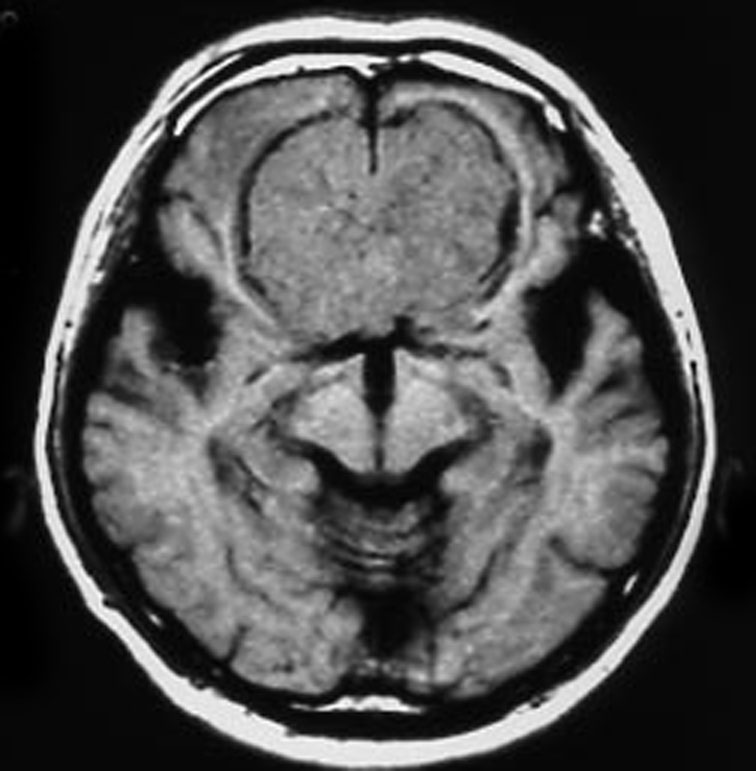

上矢状洞髄膜腫 superior sagittal sinus meningioma

また別な例です。1986年13歳の時に2度の開頭手術を受けましたが,全摘出できずにそのまま経過観察されました。

左の画像は1997年の術前のものです。これを2回に分けて全摘出しました。上矢状洞はやはり冠状縫合のあたりから静脈洞交会まで摘出しました。その下の大脳鎌も全て摘出したので,直静脈洞の上壁を開けることになり,直静脈洞からの激しい出血があり縫合して直静脈洞形成をするのが大変でした。手術後16年が経過しますが再発していませんし,社会人として普通に暮らせています。

この例が教えてくれることは,上矢状静脈洞は全長にわたり切除してしまっても,神経脱落症状を出さないで普通に生きて行かれるということです。